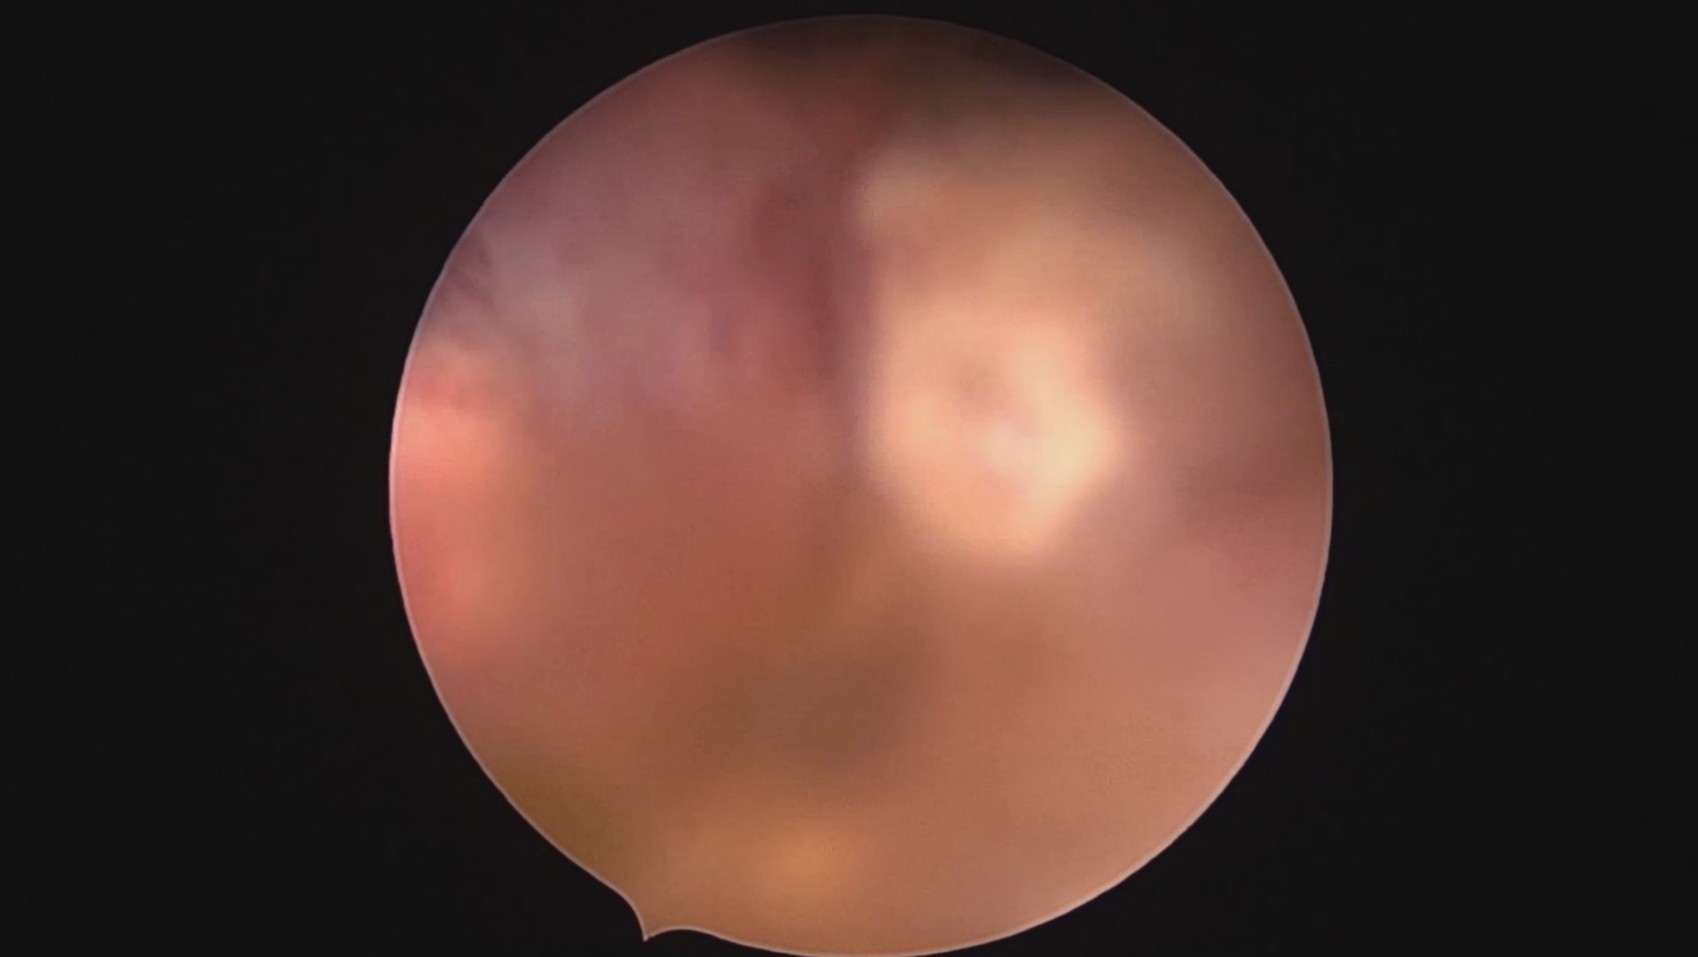

患者28岁,G7P3,顺产3次,完全纵膈子宫,单宫颈。2015年、2018年顺产,2019年左侧宫腔计划外妊娠行宫腔镜取胚及左侧宫腔放置γ环(推测既往妊娠左侧宫腔妊娠可能性大)。2023年4月带环受孕(应该为右侧宫腔妊娠),2023年12月足月阴道分娩,分娩时试图取出左侧宫腔内节育器,因操作困难,取环失败。2024年2月顺产后67天,要求取出宫内节育器,左手臂放置皮埋避孕棒。B超提示环距宫底1.1cm,环两翼分别距子宫前壁浆膜面0.4cm,距子宫后壁浆膜面0.3cm。宫腔镜术中膨宫困难,见宫颈管及宫腔少许淡黄色脓液流出,γ环逆时针旋转约80度,两臂指向左侧宫腔前后壁(2019年放置环时亦如此,因单侧宫腔前后径大于横径所致)。异物钳取出节育环,左右侧宫腔均见散在黄色机化组织,未取病检。